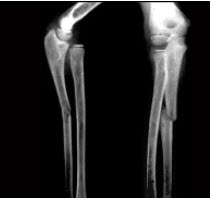

男,6岁,睡眠差、夜惊、多汗、出牙较迟、血清磷减低、血清钙减低、碱性磷酸酶升高,结合图像,最可能诊断是()

A.维生素D缺乏病

E.脆骨病